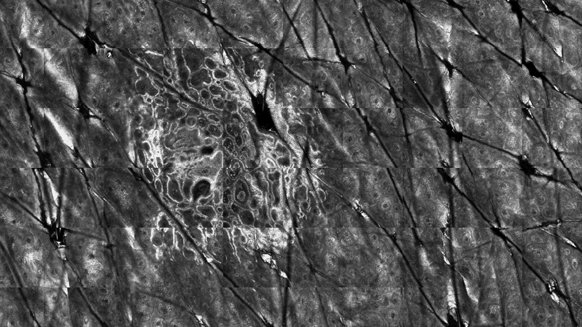

DIAGNOPTICS deals with novel tools for the diagnosis and prognosis of skin cancer. Biophotonics-based tools for in-vivo and ex-vivo analysis of lesions will be combined in a pilot diagnostic workflow, which pursues using them as consecutive filters discarding benign lesions, and confirming the malignancy of others in order to guide them to surgery only when required. The in-vivo techniques will better suggest the diagnostic of malignant lesions beyond classical dermoscopy. A combination of non-invasive mature techniques (which will deliver 3D shape, multispectral, and blood flow images) will be combined in an imaging platform for scanning lesions. Then, lesions suspicious to be malignant will be analyzed using in-vivo reflectance confocal microscopy (RCM). When malignity is confirmed and surgery required according to clinical practice, an ex-vivo analysis in the surgical room using multimodal confocal microscopy (MMC) will minimize the excision of healthy tissue around the lesion.